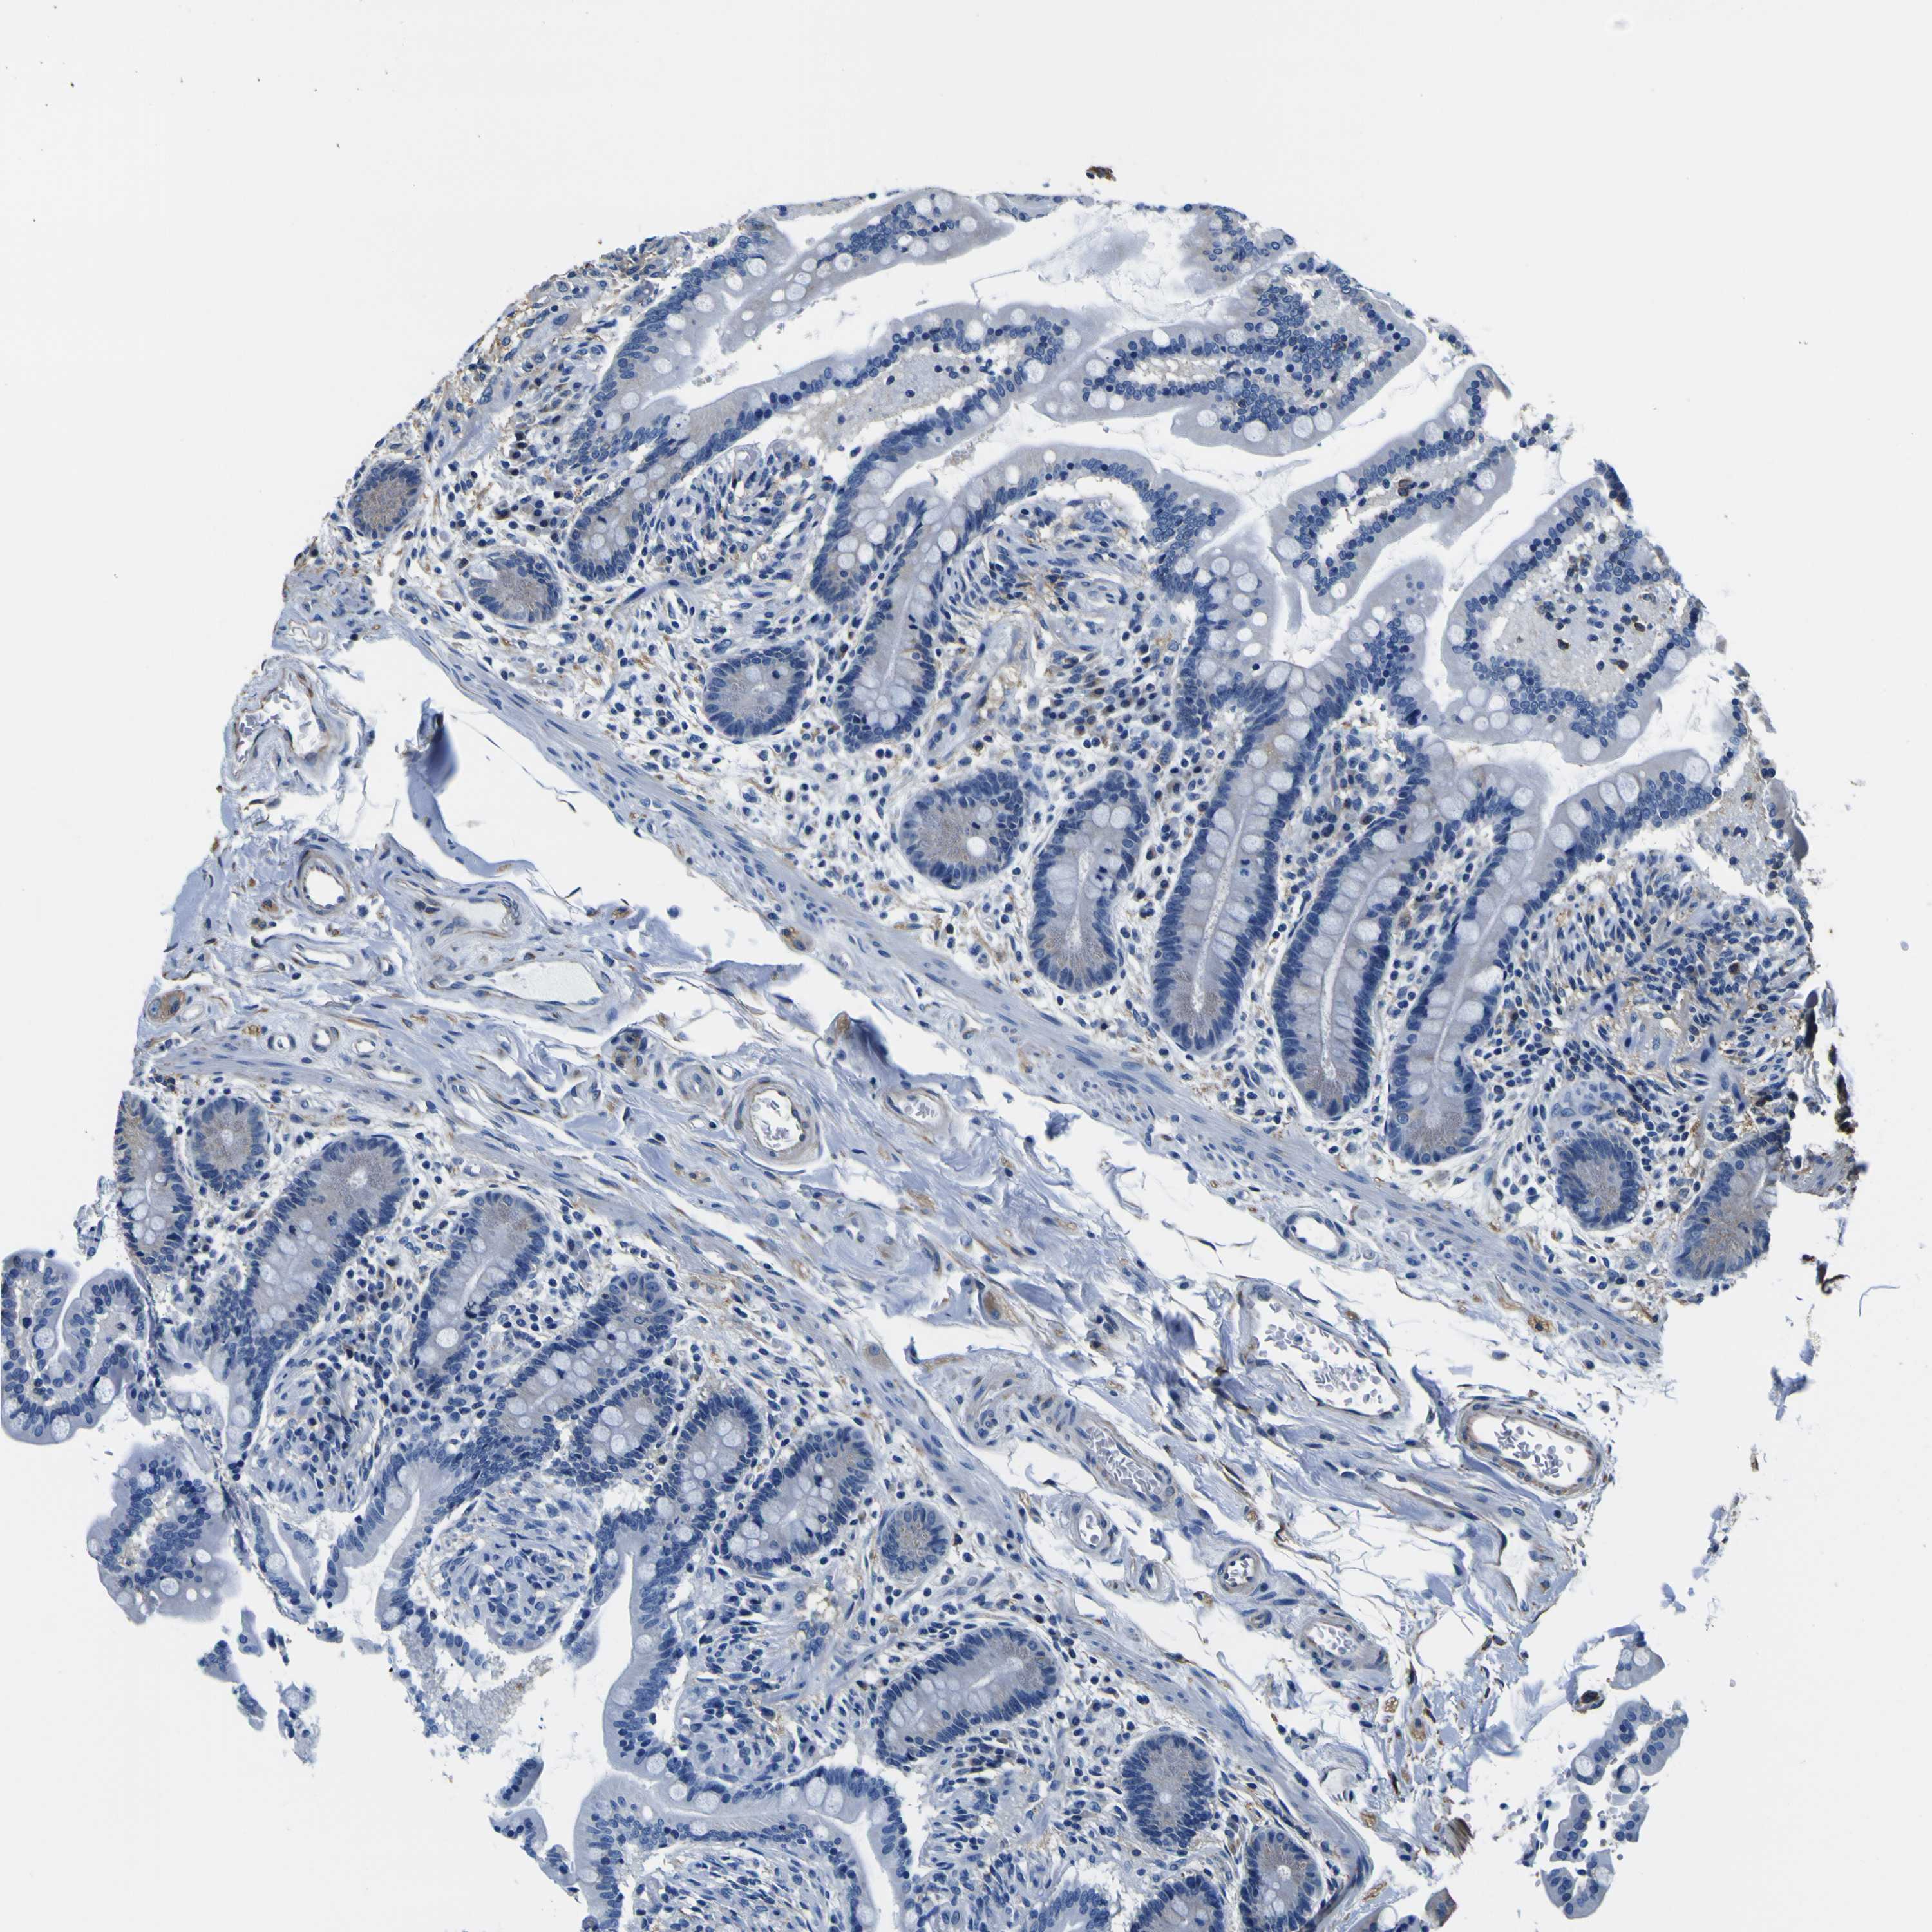

TUBA1B